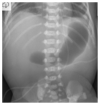

Introduction/background: Vomiting is a common chief complaint in pediatric patients seen in the Emergency Department. 1-3 Presentations include acute, chronic, and cyclic vomiting, with underlying etiologies such as toxin injection, emotional disturbances, and movement disequilibrium. 1 By understanding these various pathways, it is helpful for physicians to distinguish between gastrointestinal and non-gastrointestinal causes of vomiting. 1 Most cases of vomiting in the pediatric population are self-limiting and require only supportive treatment; however, physicians must be able to recognize red flags associated with vomiting that warrant further evaluation. 1,3 This task may be challenging for medical students and residents in emergency medicine and those with infrequent exposure to pediatric patients. Therefore, this team-based learning activity was developed to help junior learners in differentiating non-emergent and emergent cases of pediatric vomiting. This activity aids learners in formulating a differential based on age, history, and characteristics of vomiting. We also review specific causes of pediatric vomiting that physicians cannot miss including intussusception, pyloric stenosis, malrotation, intestinal atresia, and intracranial pathology.

Educational objectives: By the end of this TBL session, learners should be able to:Identify red flag symptoms that should prompt referral for urgent intervention by GI or surgical specialists.Recognize how chronicity of the vomiting can alter the differential diagnosisDescribe the varying pathways that can cause nausea and vomiting.Determine the necessity of imaging tests to confirm and possibly treat various causes of vomiting.Interpret imaging studies associated with specific causes of vomiting.